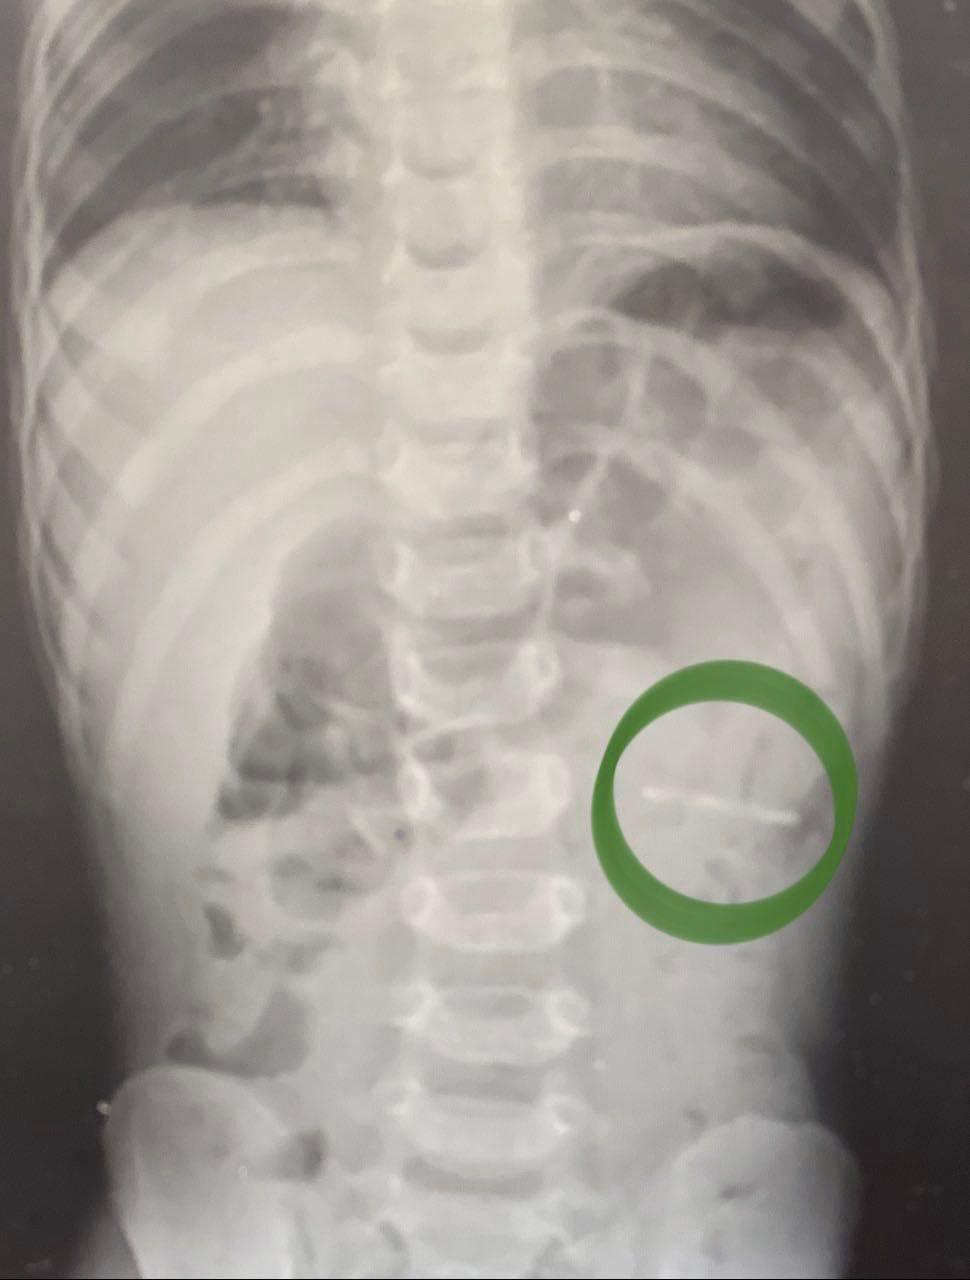

В приемное отделение Раменской больницы родители привезли полуторагодовалого сына, который по неосторожности проглотил крупный ключ от металлической банки. Незамедлительно ребёнку выполнили рентген органов брюшной полости, который показал расположение предмета — он был в желудке.

«Слизистые оболочки внутренних органов были не повреждены. При помощи эндоскопического инструмента металлический предмет с острыми краями был аккуратно извлечён. Очень важно, что при попадании в организм инородного тела лучше не пытаться вытащить его самостоятельно. Сразу обращайтесь за медицинской помощью, не вызывая рвоту и не давая есть и пить до осмотра врача», — объяснил заведующий детским хирургическим отделением Раменской больницы Владимир Хабалов.